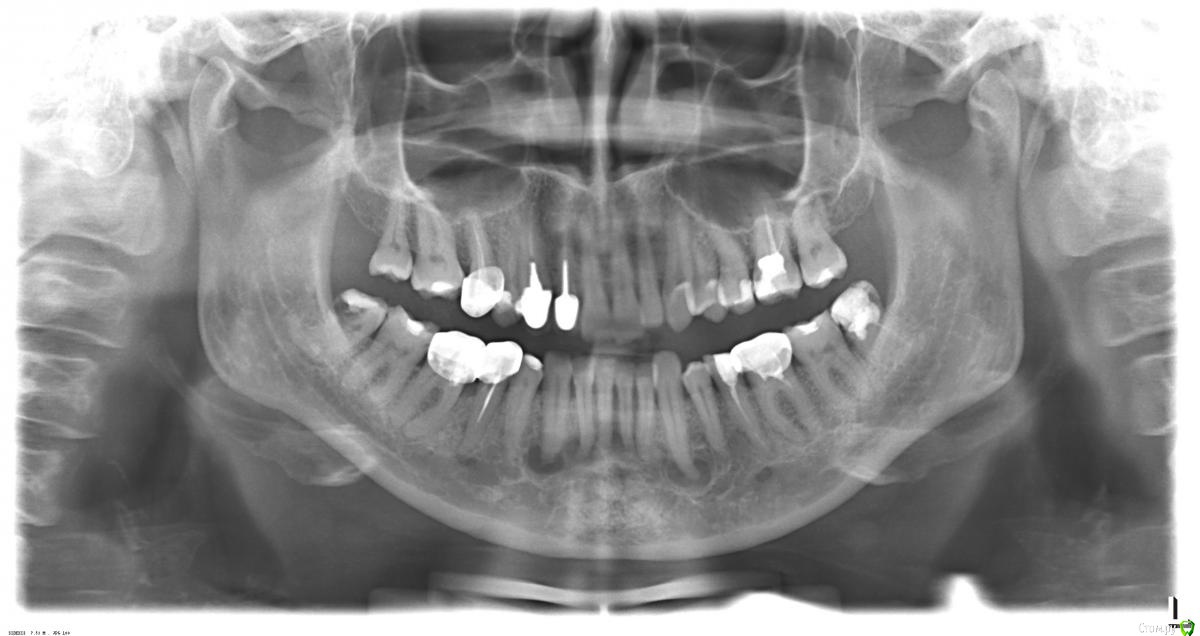

Бардо Опубликовано 8 августа, 2019 Поделиться Опубликовано 8 августа, 2019 Собственно обнаружил случайно, жалоб нет, весь фронт снизу интактен, термопроба в норме, отправил на клкт, пока жду, хотелось бы услышать мнение коллег по поводу данной ситуации. Что это вообще? Ссылка на комментарий

Kolchanov Опубликовано 8 августа, 2019 Поделиться Опубликовано 8 августа, 2019 Я думаю, что это анатомия такой. ОПТГ - довольно толстый срез, до сантиметра во фронте. По КТ понятно будет все. Ссылка на комментарий

сирена Опубликовано 8 августа, 2019 Поделиться Опубликовано 8 августа, 2019 (изменено) Периапикальная цементная дисплазия? ПЕРИАПИКАЛЬНАЯ ЦЕМЕНТНАЯ ДИСПЛАЗИЯ Реактивный процесс. Странный ответ периапикальной кости и цемента на раздражители. Частый феномен- на апексе витального(ых) зубов. Чаще у женщин. Возраст- чаще 40 лет. Чаще в переднем отделе челюстей. Обычно 2-3 зуба поражает. Обнаруживают случайно. Асимптоматично. периапикальное рентгенолюцентное поражение, как бы продолжение PDL . Зубы всегда витальны. Через некоторое время становится mixed- смешанной, потом- радиоопактной(как бы созреает). Длится это несколько лет. Вариантом ПЦД является Florid Osteus Displasia. Лечения не требуют Дифференцируют с болезнью Педжета,диффузным склерозирующим остеомиелитом, гранулема. Изменено 8 августа, 2019 пользователем сирена 7 Ссылка на комментарий

Astronaft Опубликовано 9 августа, 2019 Поделиться Опубликовано 9 августа, 2019 Это 100% цементная дисплазия.Через 20 лет очаги опаковыми станут. 1 Ссылка на комментарий